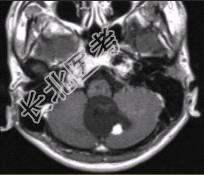

- [材料题] 男性,20岁。恶心、呕吐3d,剧烈头痛加重1d入院。MRI显示小脑下蚓部长T₁、长T₂信号影,病变可见结节状明显强化,如下图。

- 简答题1、请问该患者可能的诊断是什么?

- 简答题2、请问该病与VHL的关系是什么?